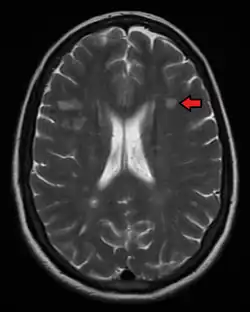

MRI

Magnetic resonance imaging (MRI) of the brain and spine may show areas of demyelination (lesions or plaques). Gadolinium can be administered intravenously as a contrast agent to highlight active plaques, and by elimination, demonstrate the existence of historical lesions not associated with symptoms at the moment of the evaluation.[94][95]

Central vein signs (CVSs) have been proposed as a good indicator of MS in comparison with other conditions causing white lesions.[96][97][98][99] One small study found fewer CVSs in older and hypertensive people.[100] Further research on CVS as a biomarker for MS is ongoing.[101]